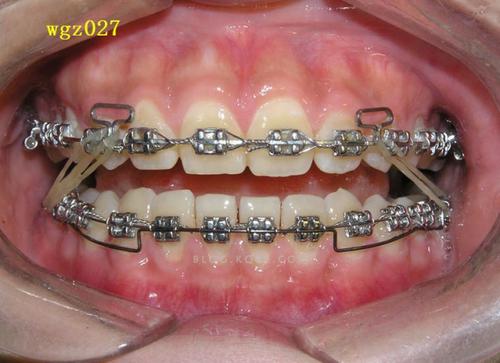

压低辅弓的核心在于通过弓丝的形变产生持续、轻柔的压低力,同时避免牙齿发生不必要的倾斜或旋转,其结构通常包括主弓丝和辅弓两部分:主弓丝(如不锈钢丝或β钛丝)提供基础支抗,辅弓(多为镍钛丝或澳丝)通过特定的弯曲形态(如“Ω”形曲、垂直曲)与托槽或附件连接,当辅弓被激活后,产生的力量通过托槽传递至牙冠,作用于牙槽骨,引导牙槽骨改建,实现牙齿压低。

力学控制是关键:辅弓的设计需确保力量中心位于牙根长轴附近,避免产生过大的力矩导致牙齿倾斜,针对前牙压低,辅弓常在侧切牙远中弯制停止曲,配合牵引钩与颌骨或后牙支抗装置连接,形成“压低-支抗”平衡系统;而后牙压低则需辅弓与磨牙带环或种植支抗钉协同,通过后牙垂直向移动为前牙压低提供空间。

- 形态设计:前牙压低辅弓常呈“”形,在侧切牙远中弯制垂直曲,配合牵引钩与颌骨或腭杆连接;后牙压低辅弓则需在磨牙区弯制后倾曲,与磨牙带环或种植钉形成锚固。

- 辅弓安装与激活:将辅弓插入托槽,通过弯制曲部或调整牵引钩位置激活力量,初始力量控制在50-100g(避免过大力量导致牙根吸收或疼痛),每4-6周复诊调整一次。